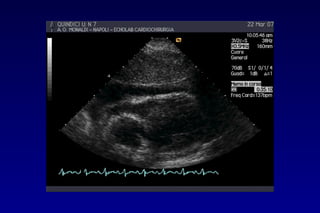

METODOLOGIA DI STUDIO DEL VERSAMENTO

PERICARDICO

• L’accumulo patologico

di fluido determina la

separazione sisto-

diastolica tra i due

foglietti con comparsa

di un’immagine a

doppio contorno che

racchiude uno spazio

relativamente privo di

echi

METODOLOGIA DI STUDIOMETODOLOGIA DI STUDIO

Il fluido tende a

raccogliersi

inizialmente

dietro la parete

posteriore del VSx

Man mano che

aumenta

la quantità del

versamento il foglietto

parietale diventa

immobile